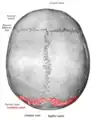

![]() Lambdoid suture, posterior view | |

The lambdoid suture, or lambdoidal suture, is a dense, fibrous connective tissue joint on the posterior aspect of the skull that connects the parietal bones with the occipital bone. It is continuous with the occipitomastoid suture.

The lambdoid suture is between the paired parietal bones and the occipital bone of the skull. It runs from the asterion on each side.